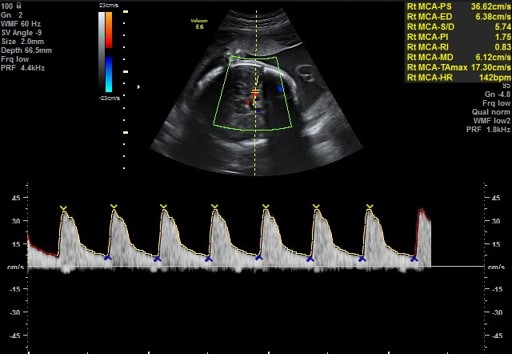

בדיקת מהירות הזרימה בעורק המוח האמצעי MCA, מנבאת די טוב את האפשרות כי קיימת אנמיה עוברית. מצב אשר לעיתים מצריך עירוי דם תוך רחמי לעובר על מנת להציל את חייו. בדיקה זו חשובה במיוחד לנשים הרות אשר פיתחו נוגדני דם מסוגים שונים.